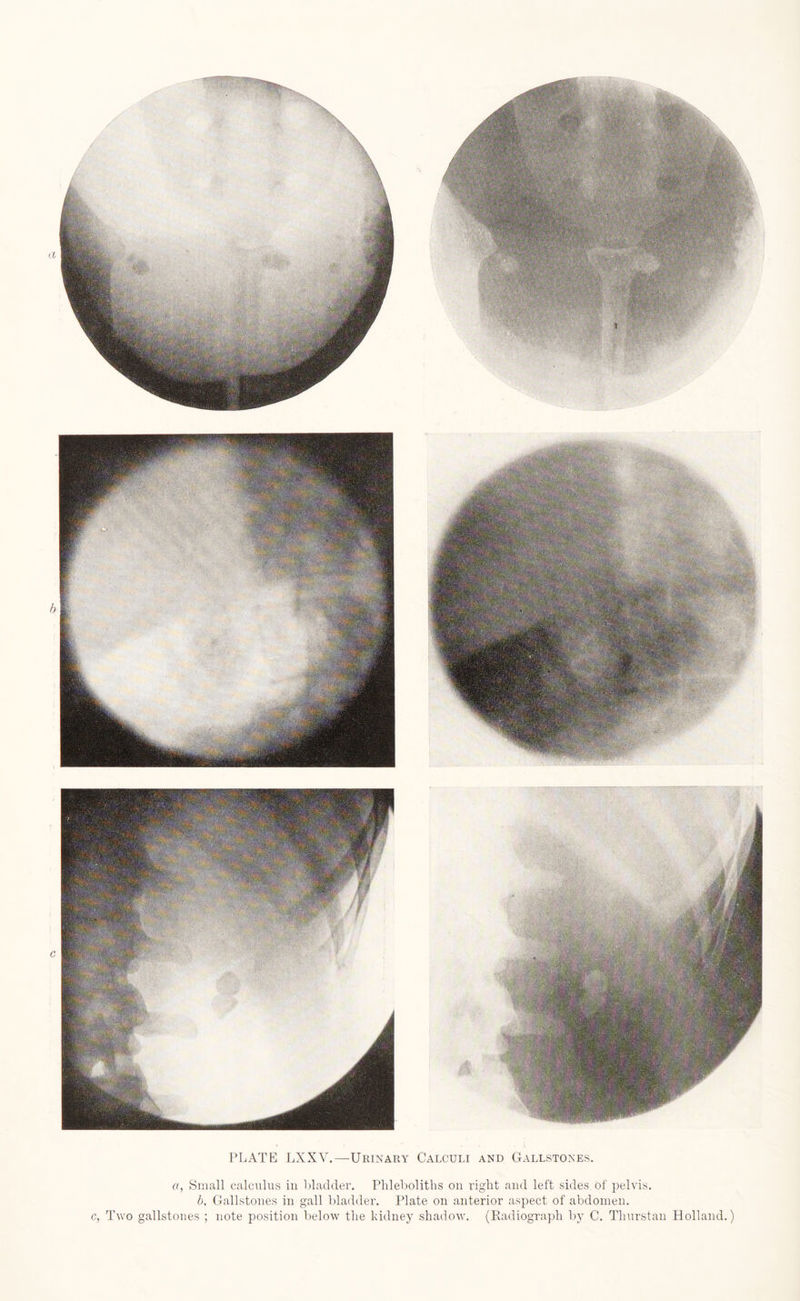

Radiography and radio-therapeutics / by Robert Knox.

496/544 page 374